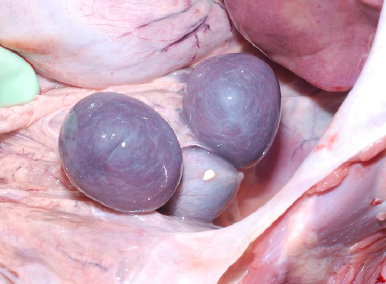

polysplenia

situs inversus totalis

rare AR condition causing abdominal and thoracic organs to be mirrored in relation to normal

asymptomatic alone and often with other anomalies